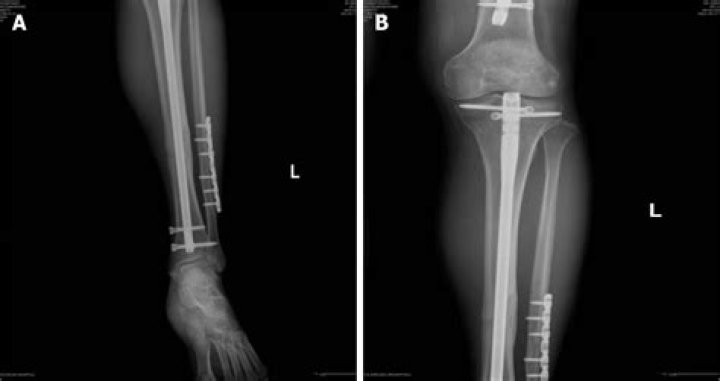

Removal of Buried Tiba Nail

The standard of care for the treatment of diaphyseal tibial fractures is an intramedullary nail (IMN). Implant removal is one of the most common procedures in bone and joint surgery, and criteria for implant removal are typically left to the treating surgeon.

Intramedullary nailing is the treatment of choice for fractures of the tibial shaft, which might necessitate the nail removal due to complications in the long-term. Although considered as a low-risk procedure, intramedullary nail removal is also associated with certain complications.

Intramedullary nailing is surgery to repair a broken bone and keep it stable. The most common bones fixed by this procedure are the thigh, shin, hip, and upper arm. A permanent nail or rod is placed into the center of the bone.